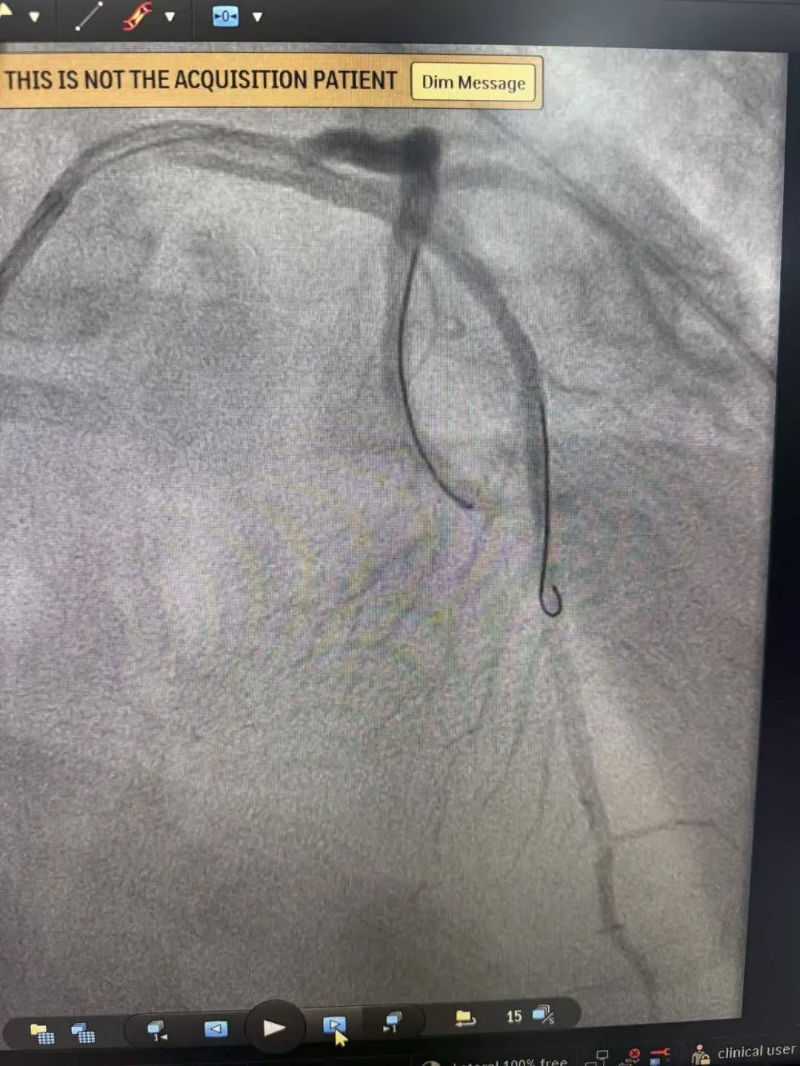

心臟恢復跳動意味著有了手術機會,患者被迅速送入介入室。介入室技師和護士早已準備就緒,惠州市中心人民醫院博羅分院麻醉科醫生也已到位。手術由溫靈武和文軼醫生共同完成。造影顯示,患者前降支開口處完全閉塞,醫生迅速開通閉塞血管并植入支架一枚,術后血流恢復良好。從患者進入介入室到血管開通,僅用時20余分鐘。

手術后血流恢復